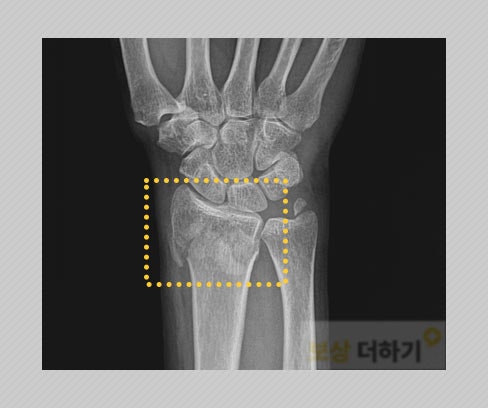

요골 하단의 골절 (분쇄) 안타깝게도 형태가 좋지 않은 손목 골절 진단을 받았는데요. 손목뼈가 여러 개로 깨지면서 부서지는 분쇄 골절이었습니다. 또한 관절면을 침범한 것으로, 추후 외상성 관절염이나 관절 운동 범위 제한 등의 후유증이 남을 확률이 높아 수술과 재활 치료가 정말 중요했습니다.

수술 및 재활 뼈의 위치를 제자리에 잡고 단단히 고정해 주는 수술을 받으셨고, 이후 재활, 약물 치료를 하셨습니다. 다행히 경과 관찰을 통해 뼈가 잘 붙었다는 것을 확인할 수 있었어요.